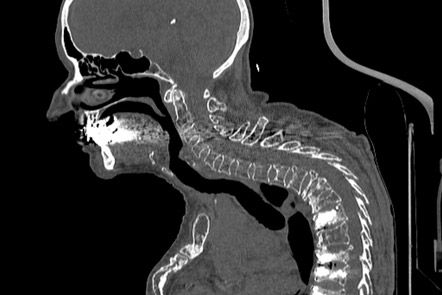

Die Computertomographie ist ein Röntgenverfahren, welches Schnittbilder des menschlichen Körpers erzeugt.

Der Patient liegt auf einer speziellen Untersuchungsliege und wird langsam durch den Detektorring gefahren. Die Röntgenröhre rotiert dabei spiralförmig um einen definierten Körperabschnitt um den Patienten , wobei ein kontinuierlicher Datenblock erzeugt wird mit der Möglichkeit, durch Nachbearbeitung (Rekonstruktionen) Schichtbilder in verschiedenen Ebenen und Schichtdicken, oder ein 3D-Modell der untersuchten Organe (z.B. Knochen, Gefäße) zu erstellen.